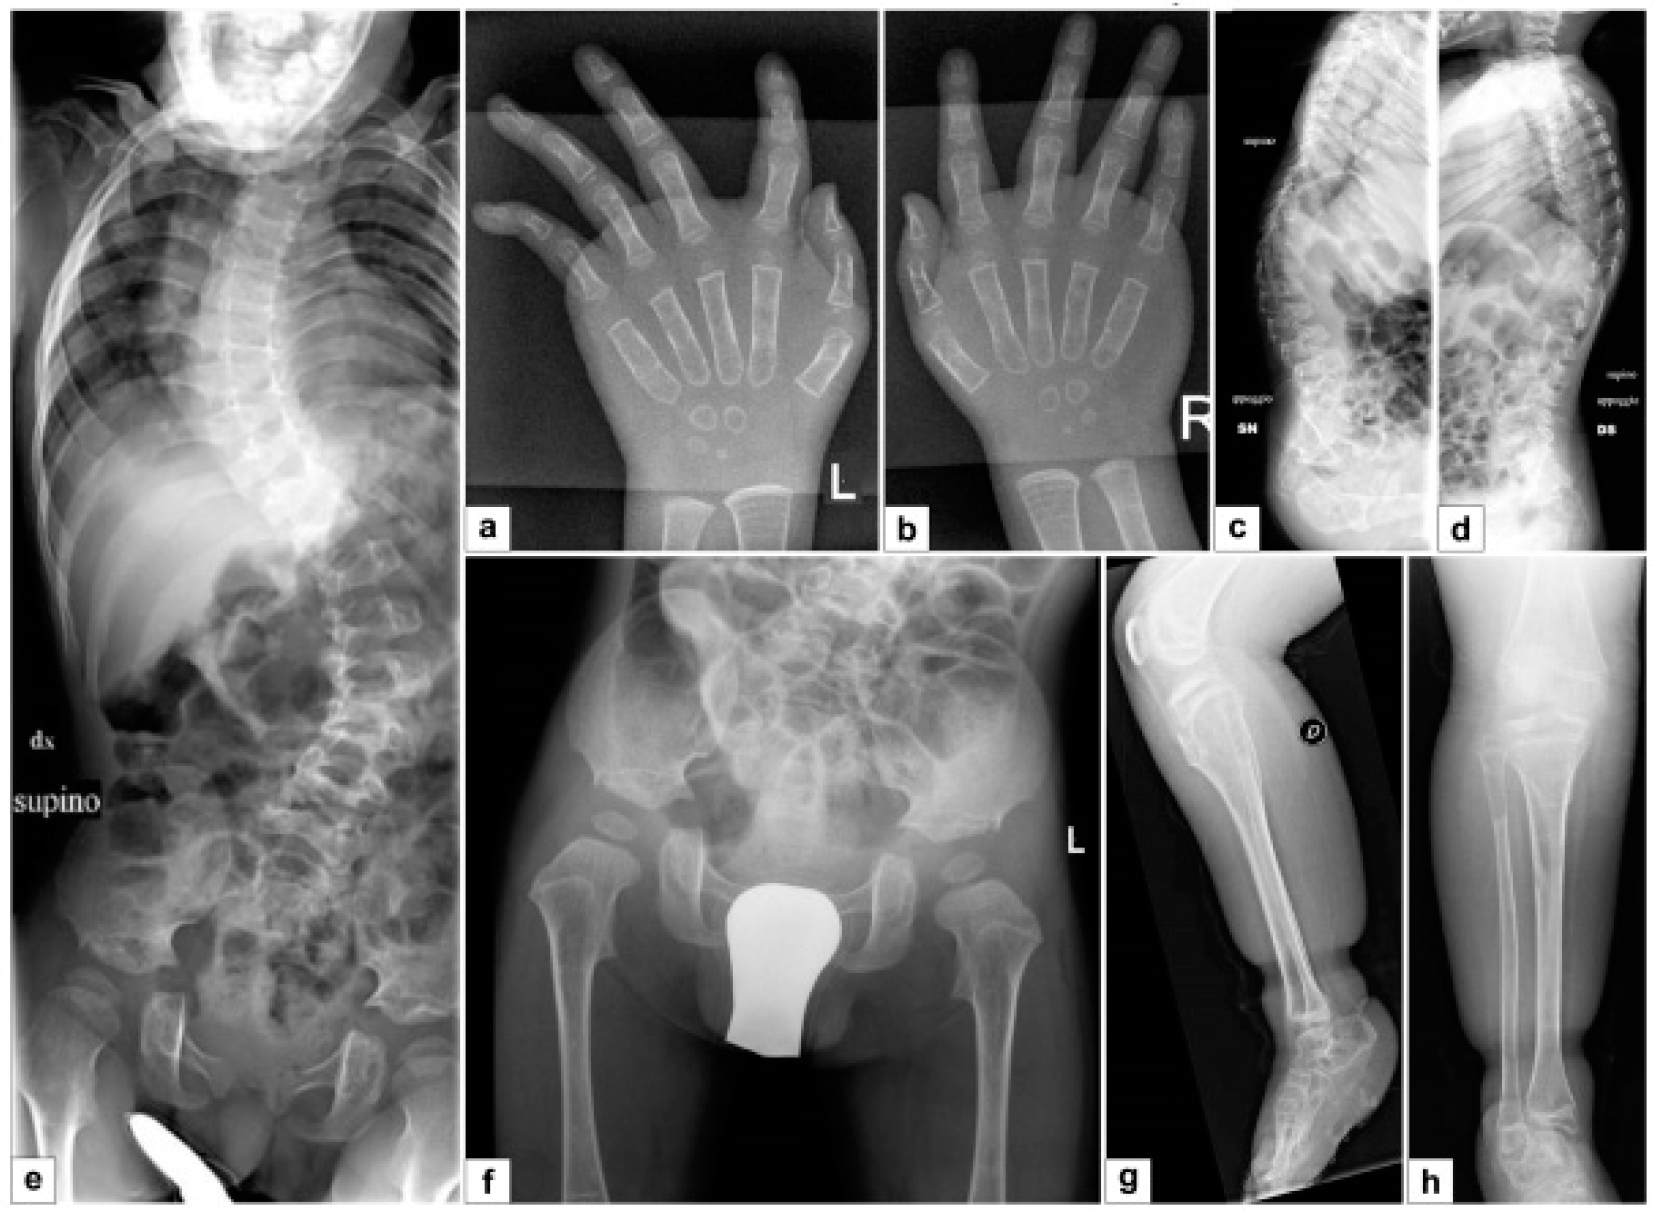

3.3. Third Patient

3.3.1. Clinical Report

4. Discussion

- the radiological signs, which are the main indicator for discriminating spEDS-B4GALT7, associated with radioulnar synostosis, and spEDS-B3GALT6, characterized by kyphoscoliosis (congenital or early onset and progressive) and by the skeletal signs of SEMDJL1 (platyspondyly, short iliac bones, elbow dislocation).